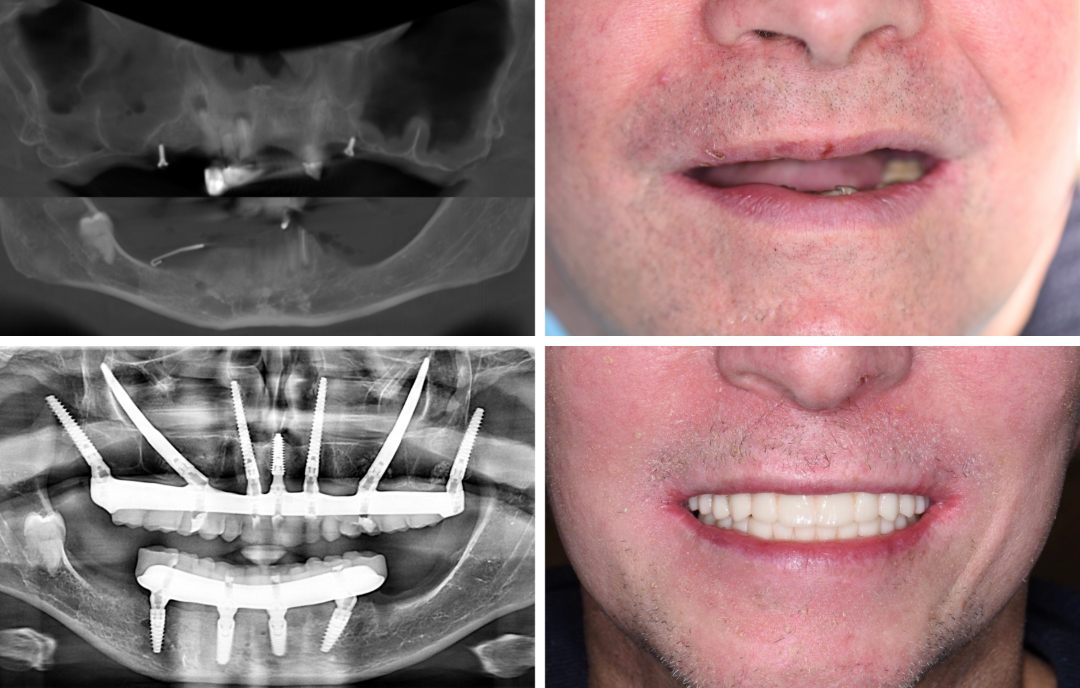

Ausgangssituation

Eine 64-jährige Patientin war viele Jahre auf der Suche nach einer festsitzenden, implantatgetragenen Lösung. Doch niemand konnte ihr eine passende Therapie anbieten.

Lösung

In ITN: Navigierte Rekonstruktion des Ober- und Unterkiefers mit Quad-Zygoma- und Pterygoid-Implantaten im Oberkiefer sowie 5 herkömmlichen Implantaten im Unterkiefer. Sofortige provisorische Brücke in beiden Kiefern – in nur einer Operation.

Vorteile

Eine vermeintlich austherapierte Patientin erhielt die gewünschte Implantatlösung – innerhalb kürzester Zeit und in beiden Kiefern. Eine Full-Arch-Rekonstruktion kann bei guter Planung in einer einzigen Sitzung erfolgen.